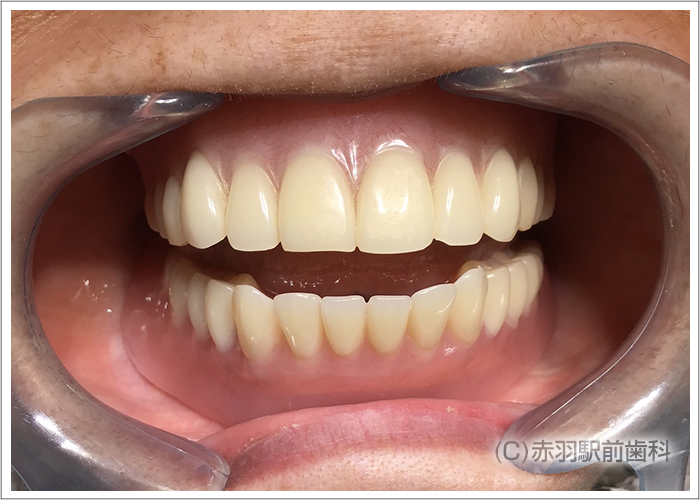

上下に最終的な上部構造の人工歯をスクリュー固定した状態です。内部の見えない部分をチタンフレームで補強して歯肉をハイブリットセラミックで加工。人工歯はジルコニアの歯を1本ずつ仕上げて完成しました。

実際に笑った時の口元です。人工歯肉の付け根は、唇の内側に隠れて見えないように計算して治療していますので、インプラントだとは他人からは判別できないです。